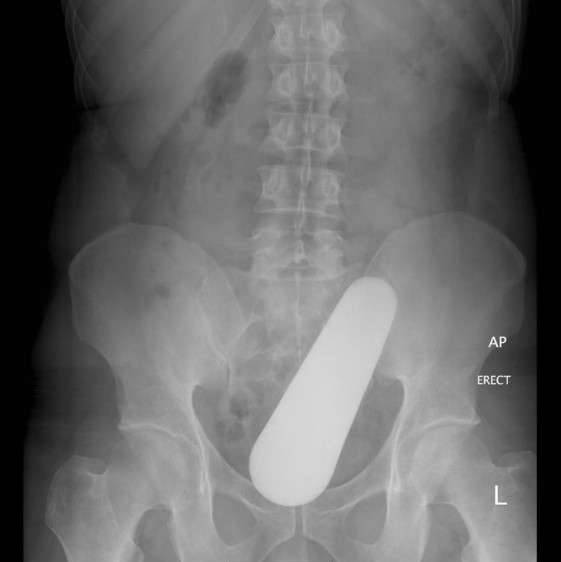

▼9.有些尴尬的病人会因为下体卡住奇怪的东西求救。这些人通常喝醉,并且非常尴尬,让他们準确描述细节非常困难,只知道他们的下体卡进了奇怪的东西。